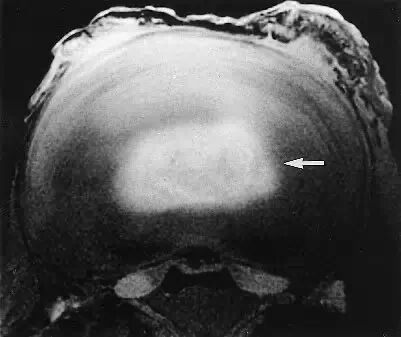

当前的MRI技术主要按质子(氢)的分布情况成像,首先反应组织的含水量。此技术的优点包括能显示椎管内肿瘤、检查全脊柱并能根据含水量的减少来确定椎间盘的退行性改变。

Szypryt等人发现在诊断脊柱疾病方面,MRI稍优于脊髓造影,MRI的准确率是88%,脊髓造影是75%; MRI在诊断椎间盘退变、肿瘤和炎症方面有明显的优势。大部分MRI扫描图像能够显示一个完整的脊柱节段(如颈段、胸段或腰段)而不是三段都显示,也能清楚地显示椎间孔部位和椎旁的软组织。

MRI非常准确,能在病人无症状时发现多种病变。Gibson等人发现在所有有症状的青少年中均有椎间盘退变,20名无症状的青少年中4名有椎间盘退变。Boden发现无症状病人中颈椎异常者在40岁以下占14%,40岁以上占28%;颈椎椎间盘退变在40岁以下为25%,60岁及60岁以上占60%。

他们研究了67例无症状病人的腰椎MRI图像,发现在60岁以下人群中腰椎间盘髓核突出者为20%,在超过60岁的人中有36%的人有髓核突出。60岁及60岁以上的被检查患者中有57%为无症状的异常;腰椎间盘退变在20~39岁年龄组为35%,50岁以上为100%。因此,必须将影像学的发现与临床的发现仔细联系在一起。